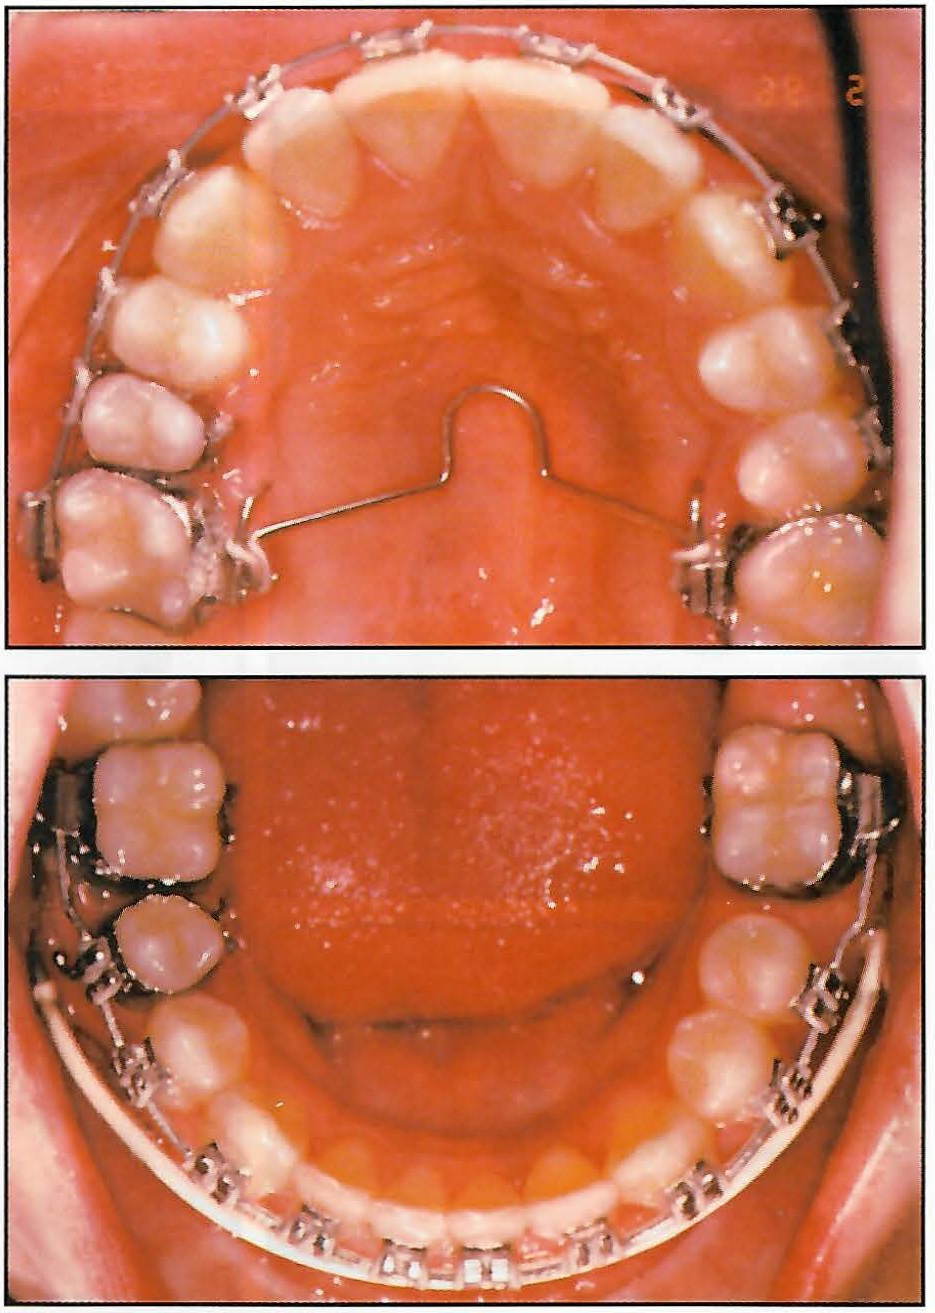

I open the professional part of the visit by asking the patients what they would like to see happen to their teeth as a result of orthodontic treatment. I then move into the actual examination. I point out the problems and the treatment I believe is needed to correct them (Fig. 6).

Fig. 6 Dr. Dischinger performs initial examination and discusses orthodontic problem.